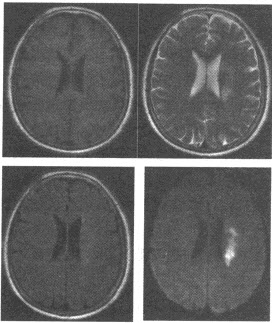

女性,53岁,右侧肢体活动不灵1天余。查体:伸舌右偏,右上下肢肌力3~4级,右侧病理征(+),MRI检查如图,最可能的诊断为()

A:脑出血

B:脑梗死

C:脑炎

D:脑胶质瘤

E:脑转移瘤